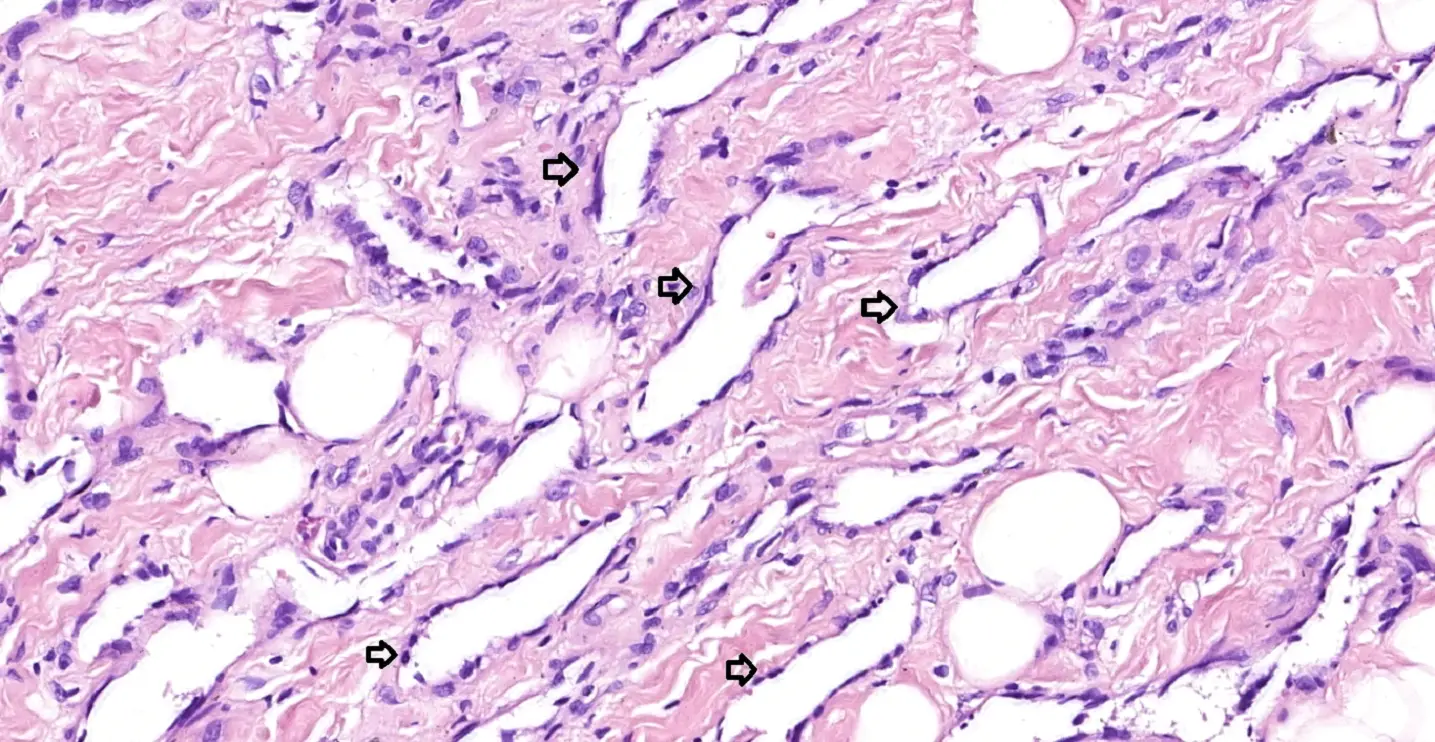

Рис. 3. Стрілками відзначені просвіти пухлинних судин. Ендотеліальні клітини сплощені, непомітні ядра, можна виявити клітини з гіперхромними ядрами, ядерна атипія мінімальна.

При мікроскопічному дослідженні тканина залози представлена численними анастомозуючими щілеподібними порожнинамии, що дифузно інфільтрують залозисту і жирову тканину молочної залози. Порожнини вистелені дещо сплощеним ендотелієм, ядра ендотеліальних клітин гіперхромні, фігури мітозів в них поодинокі. Ознак формування папіллярних вип’ячувань ендотелію в просвіт судин, формування солідних ділянок пухлини не визначалось. Пухлинні судини визначаються у інтралобулярній стромі, що є важливим моментом у діагностиці первинних ангіосарком молочної залози.